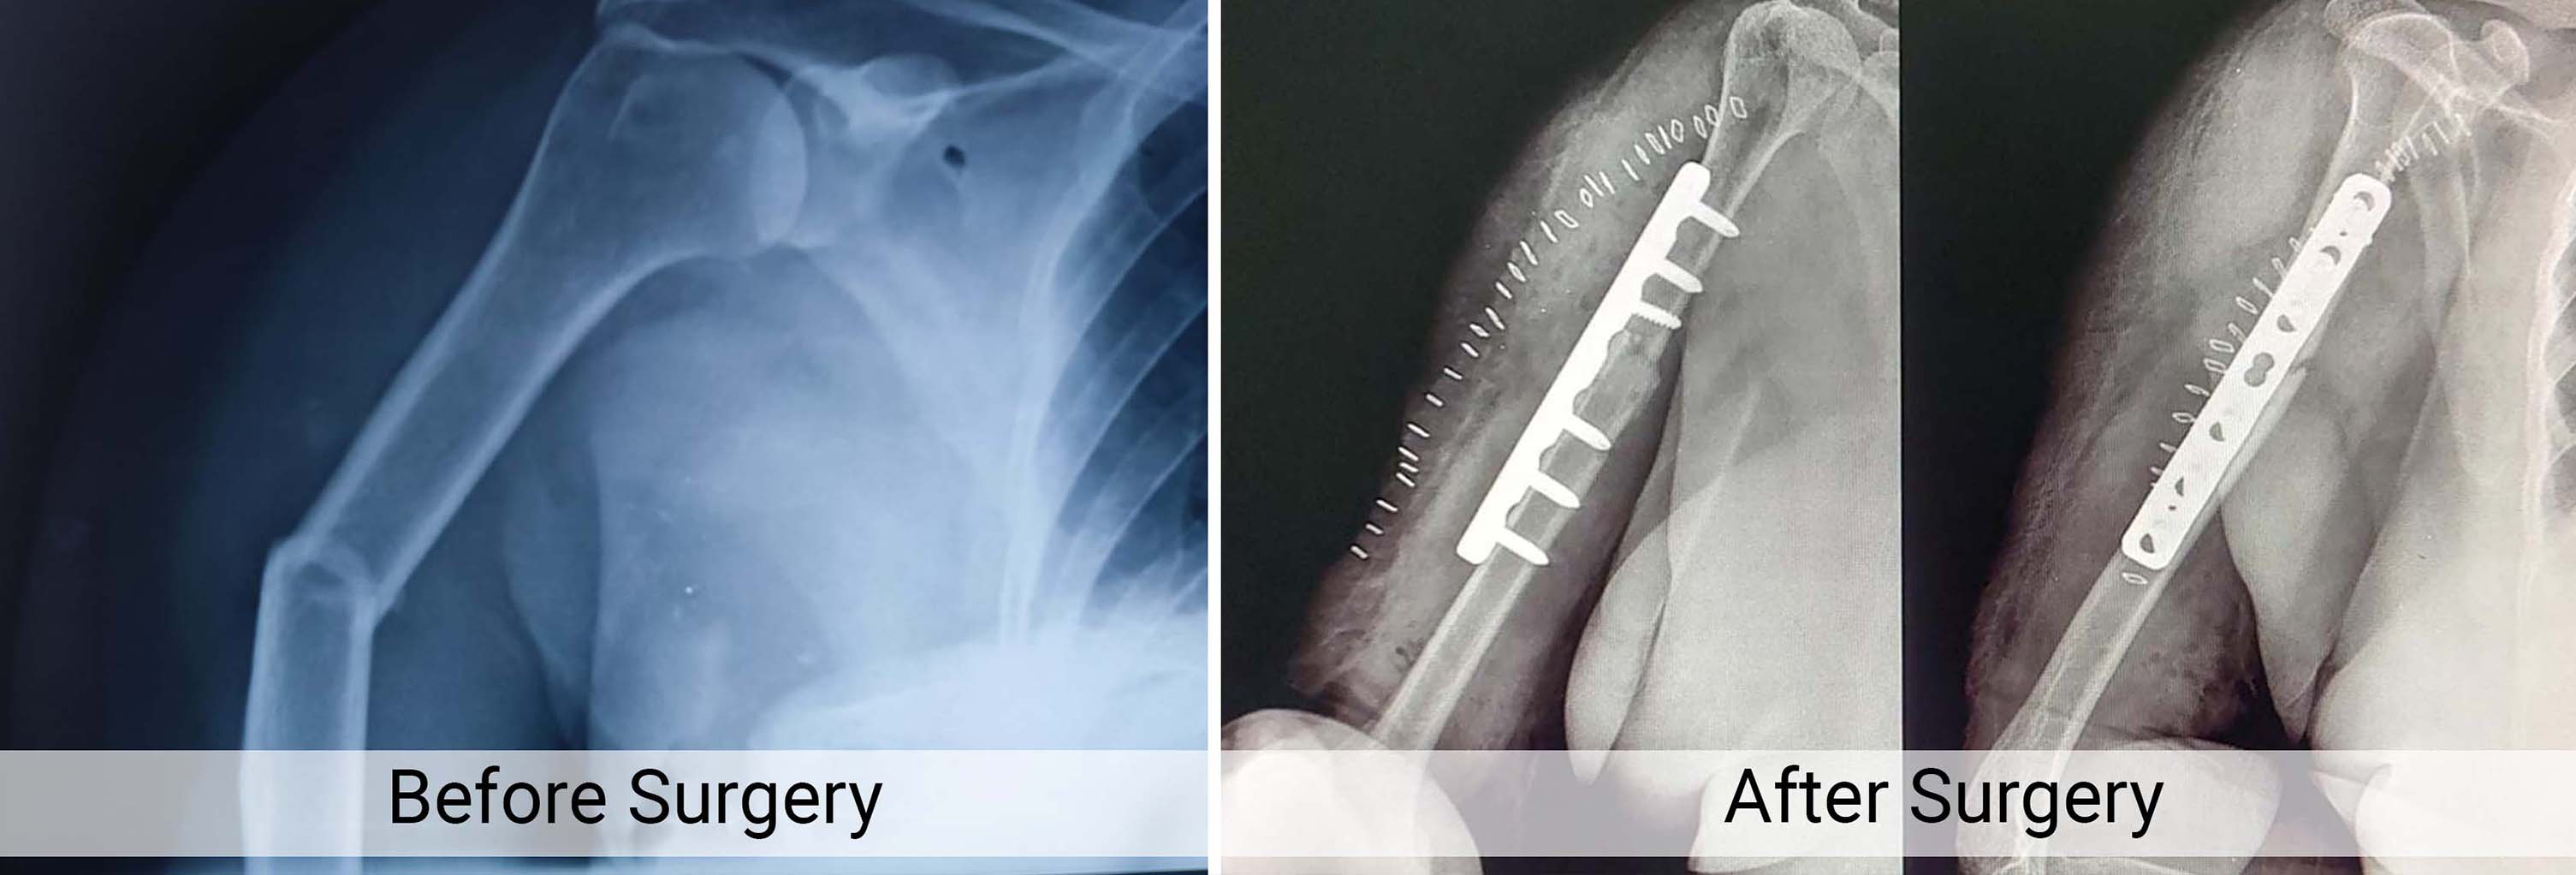

Trauma Fracture